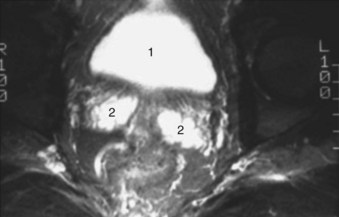

Figure 2–38 Axial T2-weighted magnetic resonance image of the male pelvis through the prostate gland and adjacent structures. 1, urinary bladder; 2, lateral lobes of prostate; 3, verumontanum; 4, striated urethral sphincter; 5, inferior pubic ramus; 6, corpus spongiosum in cross section; 7, external iliac artery.